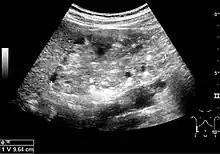

Complex cysts can have membranes dividing the fluid-filled center with internal echoes, calcifications or irregular thickened walls. The complex cyst can be further evaluated with Doppler US, and for Bosniak classification and follow-up of complex cysts, either contrast-enhanced ultrasound (CEUS) or contrast CT is used (Figure 6). The Bosniak classification is divided into four groups going from I, corresponding to a simple cyst, to IV, corresponding to a cyst with solid parts and an 85–100% risk of malignancy.[1] In polycystic kidney disease, multiple cysts of varying size in close contact with each other are seen filling virtually the entire renal region. In advanced stages of this disease, the kidneys are enlarged with a lack of corticomedullary differentiation (Figure 7).[1]